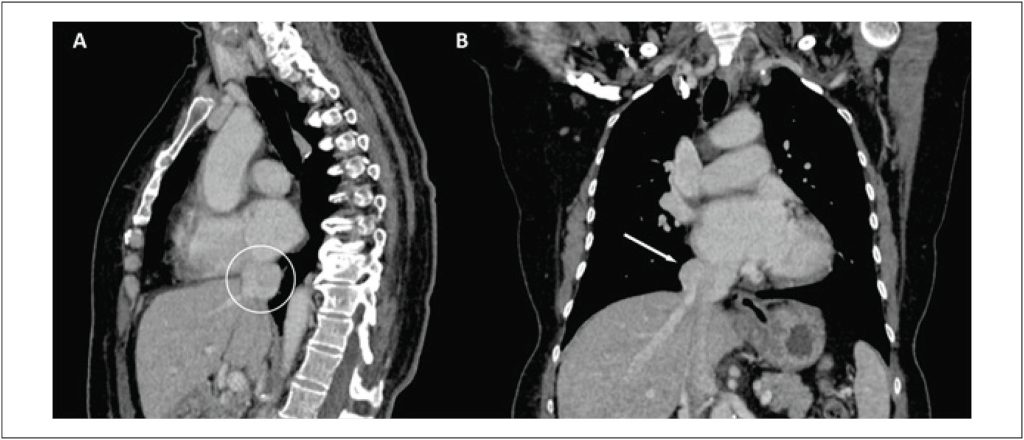

Aneurisma da Porção Supra-Hepática da Veia Cava Inferior: Relato de Caso

Os aneurismas da veia cava inferior (VCI) constituem achados raros no sistema cardiovascular e podem manifestar-se com sinais e sintomas variados. Em muitos casos, os pacientes permanecem assintomáticos, o que contribui para a dificuldade no estabelecimento do diagnóstico. Aneurismas venosos são definidos como uma dilatação anormal e persistente de uma veia em uma região focal, apresentando diâmetro pelo menos duas vezes maior que o considerado normal. Nesse contexto, o aneurisma da VCI representa uma forma específica de aneurisma venoso. A relevância do presente relato de caso é evidenciada pela raridade dessa condição, visto que, até 2021, aproximadamente 70 casos haviam sido descritos na literatura.